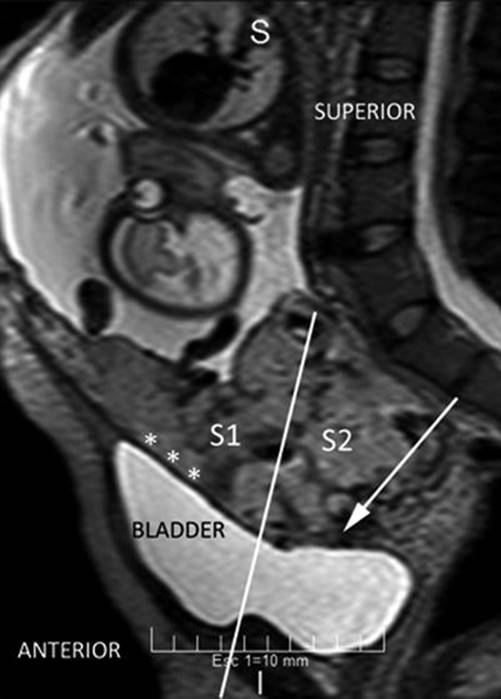

Identification of S1 and S2 areas can be established by pMRI, sagittal slice (Fig. 14.10). A line that perpendicularly crosses the middle of the posterior bladder wall determines an upper area named S1, which mainly corresponds to the uterine body, and an area below this line, named S2, which involves the lower segment, cervix and upper vagina [9]. Most part of AIP is located in S2 area, which also explained the high rate of failures with the use of uterine or internal iliac vascular control.

Fig. 14.10

Sagittal MRI T2 image: perpendicular plane which divide the posterior bladder wall determine an areas S1 and S2. White arrow shows an interrupted myometrium. Lagoons and vessels are clearly visible in the myometrial-bladder interphase